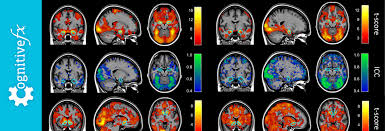

<p>fMRI (Functional MRI)</p>

fMRI (Functional MRI)

• detects changes in blood flow and identifies regions of the brain that are active during a given task

• it is useful to see what is lighting up but it is not time locked

• this means the brain will react slower after the different stimuli